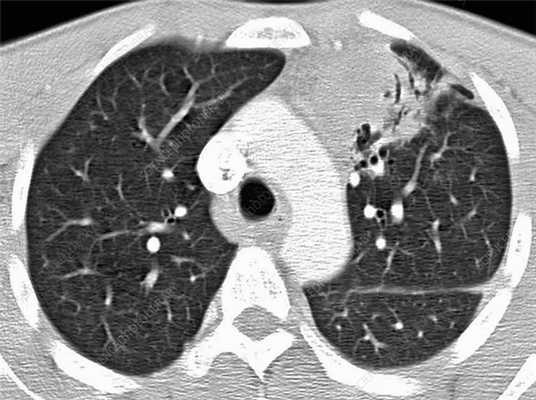

Посттрансплантационная лимфопролиферативная болезнь на рентгенограмме, КТ органов грудной клетки

Лимфома легких на КТ

Признаки лимфомы легких особенно выражены на четвертой стадии заболевания, когда болезнь поражает дыхательный орган. На КТ при этом будут видны увеличенные лимфоузлы, формирующие цепочки, конгломераты. При этом у пациента может также наблюдаться отек легких. Однако высокая разрешающая способность КТ позволяет выявить лимфому на ранней, первой стадии.

На КТ лимфомы, как и любые уплотнения, визуализируются сравнительно более светлым цветом. В норме воздушная легочная паренхима практически однородного темного цвета. Иногда таких уплотнений несколько и они диссеминированны. Контуры лимфомы четкие и ровные. Вокруг патологических очагов обнаруживаются участки «матового стекла».